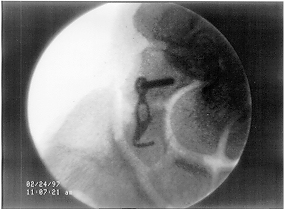

Ecco un esempio di tale placca in sede:

Miniplacca profyle